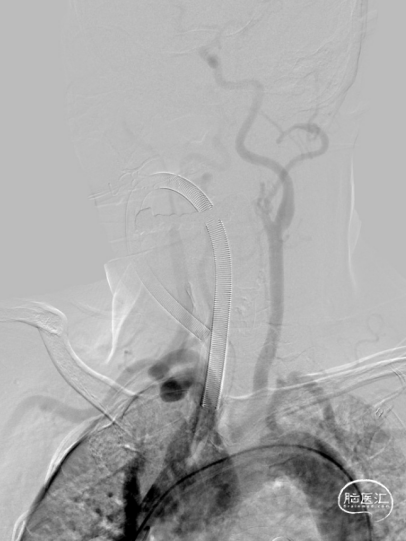

造影显示RICA:C1段起始部闭塞,残端呈锥形,TICI分级0级;RMCA未显影,远端由RACA经皮层支少量代偿,ASITN分级1-2级。

将Catalyst7 132中间导管经导引导管送至于RICA C1段起始部闭塞处,采用ADAPT技术自C1段至C4段反复抽吸取栓,取出大量暗红色血栓。

手推冒烟见RICA C1-C5段显影,C5段以远闭塞。将Pro-18微导管在Synchro(0.014×200mm)微导丝引导下送至RMCA M2段,微导管冒烟示远端血流通畅。将Trevo XP(4×20mm)取栓支架于M1段远端向RICA末端释放,采用SWIM技术取栓1次,并同时将中间导管送至颈内动脉末端抽吸。抽出数枚暗红色血栓。

造影见RICA再通,RMCA M1段近端重度狭窄,约90%。

观察10分钟后,狭窄较前加重,局部不规则充盈缺损。术中即刻DynaCT未见造影剂染色。

将Synchro(0.014×300cm)微导丝外衬Gateway(2.0×15mm)球囊缓慢通过RMCA M1段狭窄处,球囊定位于RMCA狭窄处缓慢扩张,压力6atm。采用交换技术置入灌注微导管,并将4.0×16mm支架定位于狭窄处释放。

复查造影见支架展开良好,支架内及远端血流通畅,TICI分级3级。术顺,术毕,Proglide缝合术口。